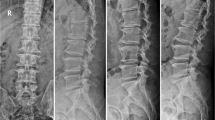

To evaluate the factors that could influence US-guided PELD, we divided the patients into different subgroups according to the height of the iliac crest and BMI. Among the L5–S1 cases, the patients were divided according to iliac crest height into those with a high crest, indicating that the iliac crest was higher than the L5 pedicle, and those with a low crest, indicating that the iliac crest was lower than the L5 pedicle.

Factors influencing the puncture and cannulation times in the US group

The puncture times for the patients treated at the L5–S1 level were significantly longer than those for the patients treated at the L4–5 and L3–4 levels. In addition, the puncture times for the patients with a BMI greater than 28 kg/m2 were significantly longer than those for the patients with a BMI less than 28 kg/m2. In cases treated at the L5–S1 level, the puncture times for the patients with a high iliac crest were significantly longer than those in the patients with a low iliac crest. Regarding the cannulation time, no significant differences were found among the patients according to different treatment levels, BMI values, or iliac crest heights. Table 3 shows the factors influencing the puncture and cannulation times in the US-guided PELD procedures.